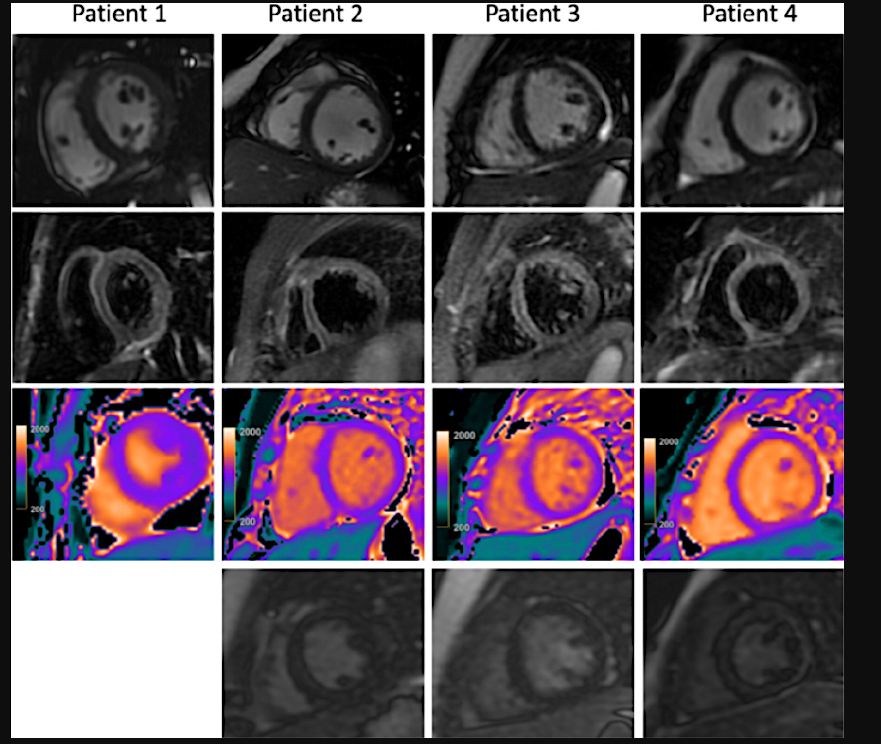

This photo gallery shows the variety of radiological presentations of COVID-19 (SARS-CoV-2) in medical imaging, including computed tomography (CT), radiograph X-rays, ultrasound, echocardiograms and magnetic resonance imaging (MRI). The radiology images show examples of typical COVID pneumonia in the lungs and the numerous complications the virus causes in the body in multiple organs, including the brain, kidneys, heart, abdomen and vascular system.

Ultrasound, especially hand-held ultrasound imaging devices, have become a primary imaging modality for novel coronavirus because of the ease to bag the device and sterilize it after use. CT and mobile X-ray systems are also used as front-line imaging systems for COVID-positive or suspected COVID patients.